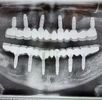

Implant treatment